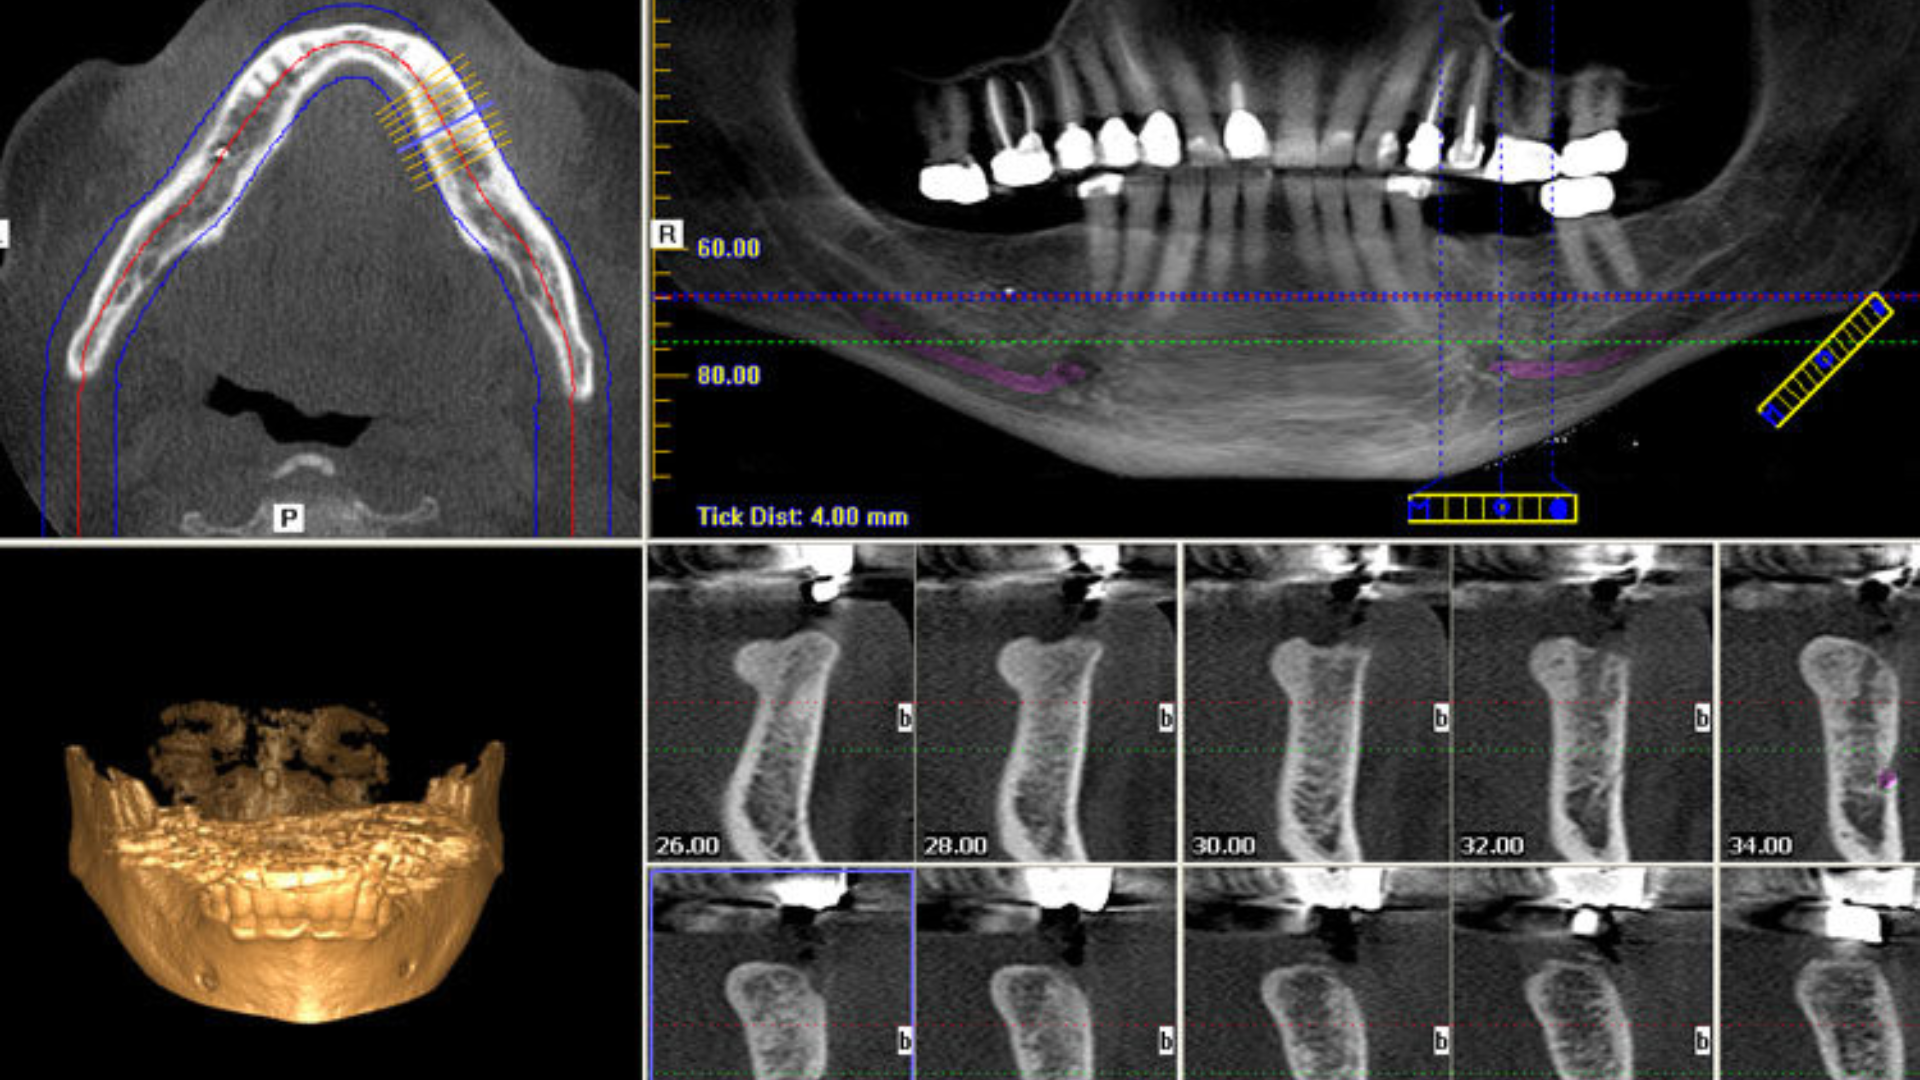

Chụp CT ConeBeam là kỹ thuật chẩn đoán hình ảnh sử dụng chùm tia X hình nón kết hợp với hệ thống máy tính để tạo ra hình ảnh ba chiều (3D) của răng, xương hàm, khớp thái dương - hàm và các cấu trúc lân cận.

Hình ảnh CT ConeBeam cho phép bác sĩ quan sát cấu trúc giải phẫu theo nhiều mặt cắt khác nhau, giúp đánh giá chính xác vị trí, hình dạng và mối liên quan của các cấu trúc trong không gian ba chiều.

Lập kế hoạch cấy ghép implant

CT giúp đánh giá chiều cao, chiều rộng xương hàm, xác định vị trí dây thần kinh răng dưới, khoảng cách đến xoang hàm và lựa chọn kích thước cùng vị trí implant phù hợp. Nhờ đó, cấy ghép implant trở nên an toàn và chính xác hơn.

Đánh giá răng mọc ngầm, răng khôn

CT ConeBeam giúp xác định vị trí răng ngầm, đánh giá hướng mọc, mối liên quan với răng kế cận và dây thần kinh, thông tin đặc biệt quan trọng trước khi nhổ răng khôn phức tạp.